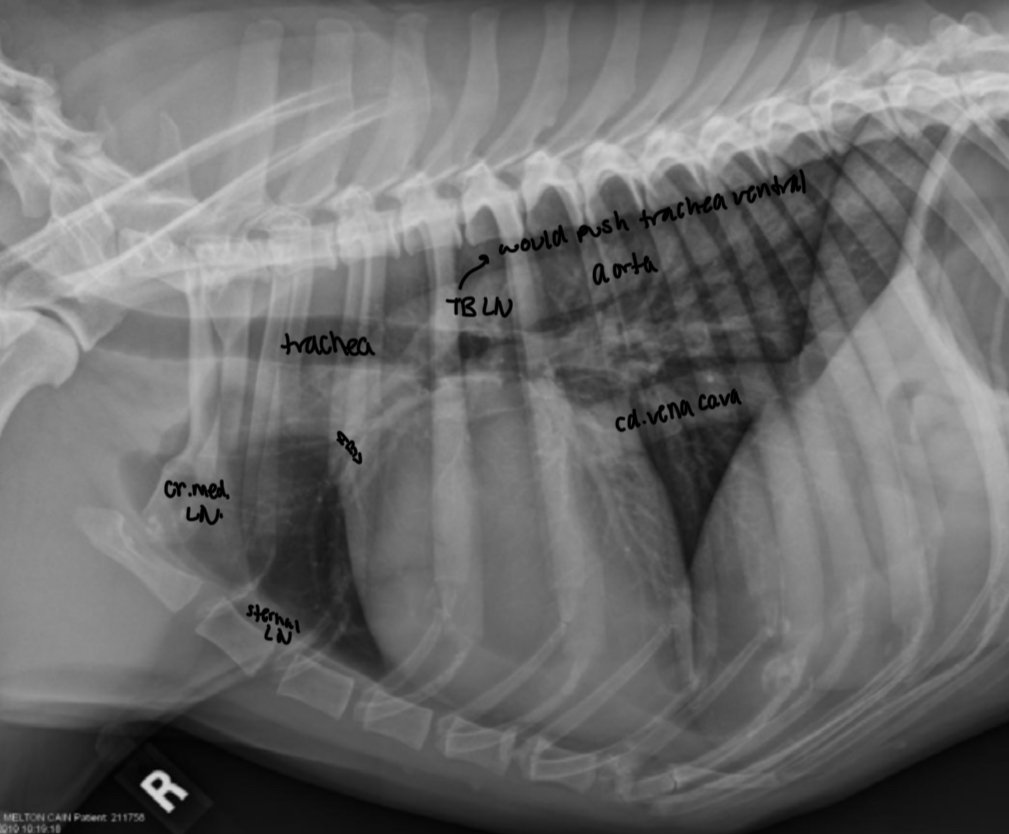

What makes up the dorsal 1/3 and ventral 2/3 cranial border on lat view

Dorsal 1/3

- MPA

- right auricle

- ascending aorta

Ventral 2/3

- wall of right ventricle and outflow tract

What makes up the dorsal 1/3 and ventral 2/3 of the caudal border on a lateral view

- left atrium (obscured by overlying pulmonary vessels)

- sulcus at junction of left atrium and left ventricle

- left ventricular free wall

where is the aorta and cd. Vena cava located on VD

Aorta - superimposed with spine and heart on VD

Cd. Vena cava - superimposed with accessory lung lobe in right cd. Thorax on VD

Where is left caudal pulmonary artery and right caudal pulmonary artery located in respect to trachea

Left - dorsal to tracheal bifurcation

Right - ventral to tracheal bifurcation